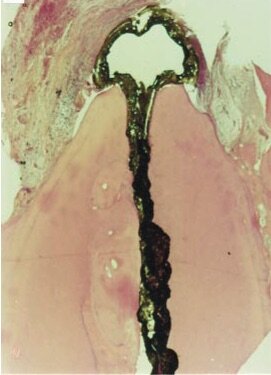

The results of an in vivo histological study involving apical and periapical tissues following root canal therapy after different observation periods demonstrated the most favourable histological conditions when the instrumentation and obturation remained at or short of the apical constriction. This was the case in the presence of vital or necrotic pulps, also when bacteria had penetrated the foramen and were present in the periapical tissues.